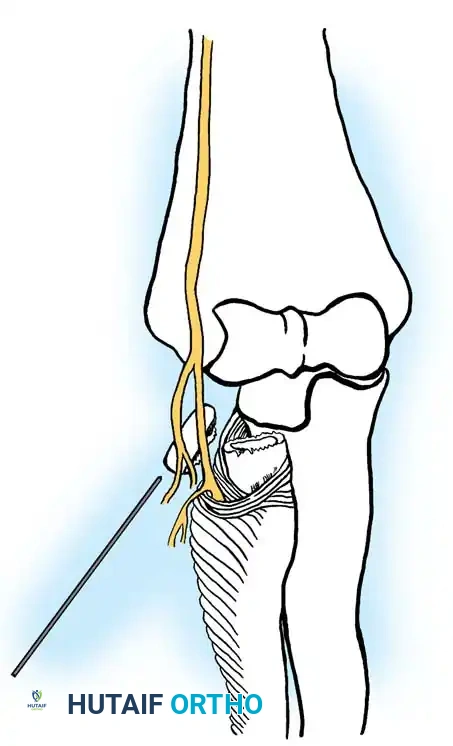

Anatomical Pitfall: During percutaneous reduction, the Kirschner wire must be introduced on the ulnar side of the radius. Introducing the wire laterally risks iatrogenic injury to the deep branch of the radial nerve (posterior interosseous nerve) as it traverses the arcade of Frohse.

Fig. 33-43 Radial neck fracture in relation to arcade of Frohse.